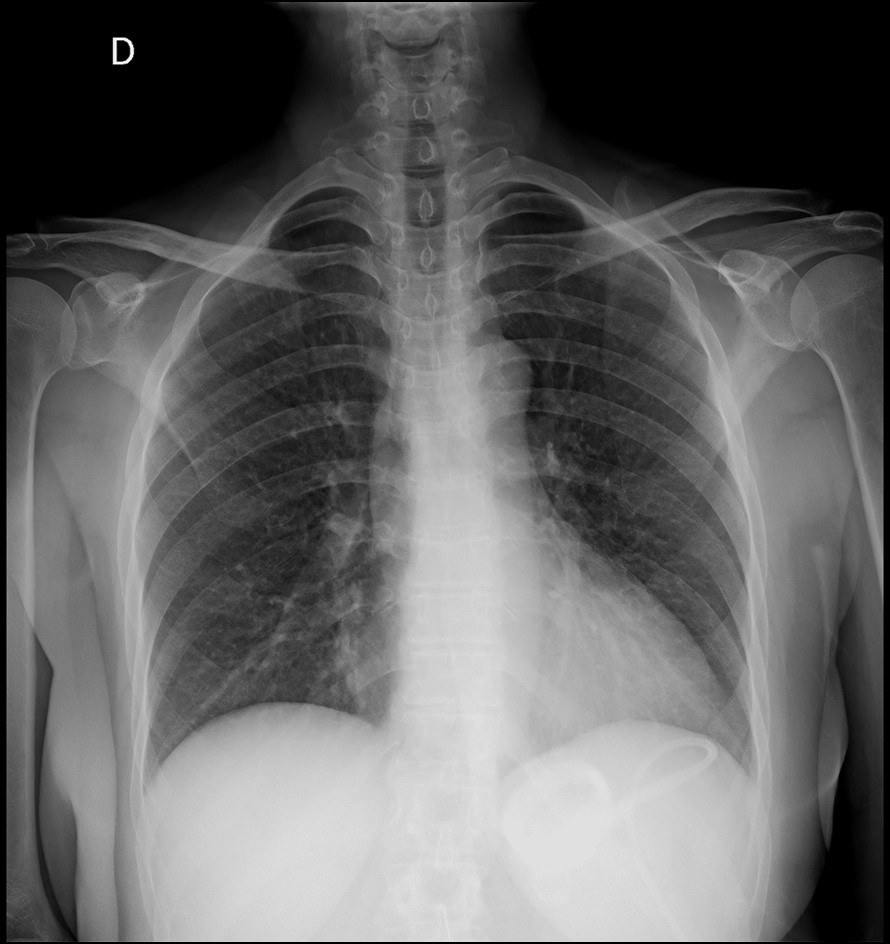

Figura 1: Banda gástrica en hipocondrio izquierdo.